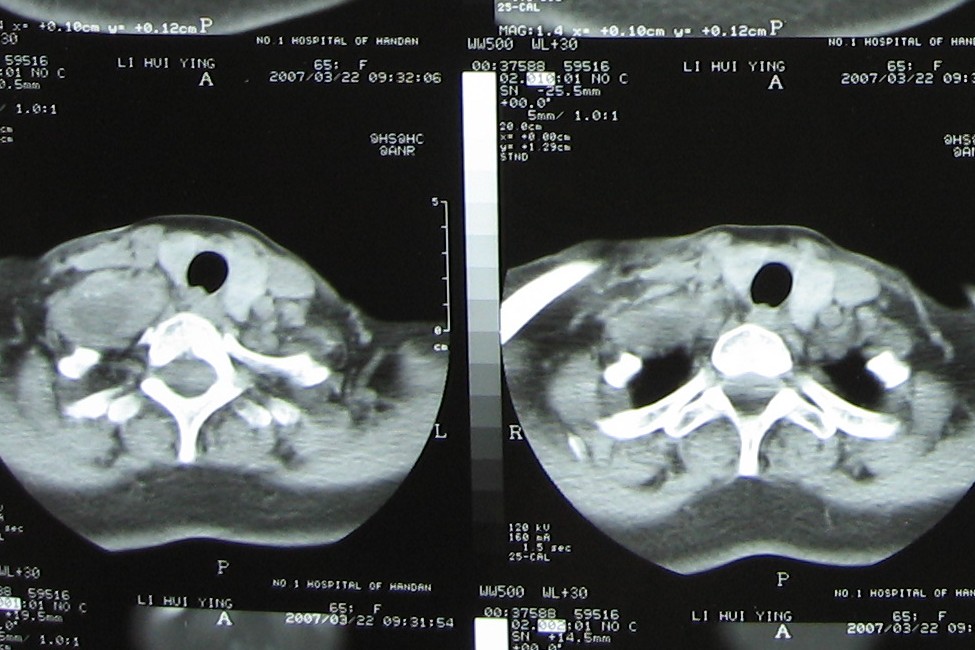

标题: CT7396:病人女65岁主因颈部肿疼伴上肢麻木4年近来加重入院 [打印本页]

标题: CT7396:病人女65岁主因颈部肿疼伴上肢麻木4年近来加重入院

支持考虑:神经原性肿瘤。(右侧椎间孔扩大,椎板破坏,局部明显的软组织肿块,并与椎管 神经根关系密切。)

1、考虑神经原性肿瘤。

2、提示c6不稳。

支持考虑:神经源性肿瘤(右侧椎间孔扩大,椎板破坏,局部明显的软组织肿块,并与椎管神经根关系密切)。